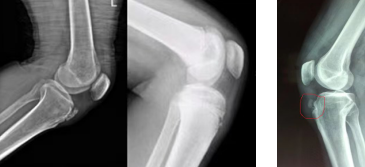

这种疾病的病因是膝关节在运动过程中,髌腱会对胫骨结节发生牵拉,由于儿童肌腱强度会比骨头更强一些,长期的牵拉刺激导致髌韧带止点的胫骨结节附着处发生炎症反应,而引起疼痛不适。一般通过患儿症状及X线片表现即可明确诊断。